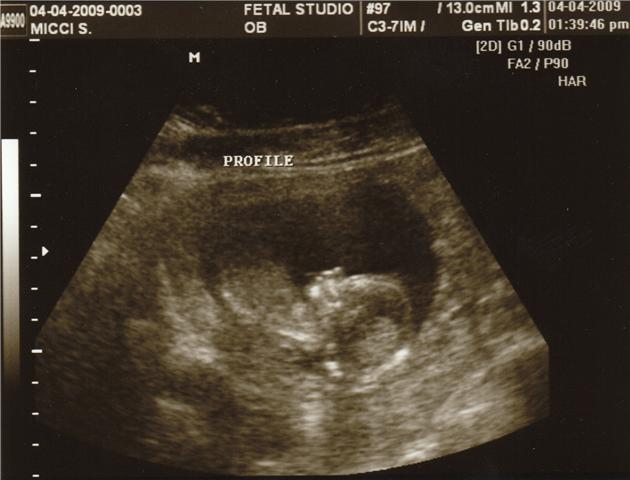

Spur of the moment on Saturday between General Conference sessions, Jazz and I ran to a 3D Ultrasound place in Sandy to get a peek at our baby. Ever since we found out we were expecting, we have been DYING to find out the gender of this little fetus. I really don’t know how people wait all 40 weeks, I would seriously explode. Patience just does not come easily to me. So we broke down and paid the extra money to get an early preview of our offspring.

It’s a GIRL! From what the doctor saw, he said she was a healthy 15 week baby girl, we got to see arms and legs and her little nose and 5 fingers (so we know she has at least one good hand). She had the hiccups while we were watching her on screen and it was incredible to see her whole body jump around like she was showing off for us. Maybe she has some of my competitiveness….

Without further adieu, here is Baby Girl (I don’t have to call her “it” or “fetus” or “herm” anymore!)